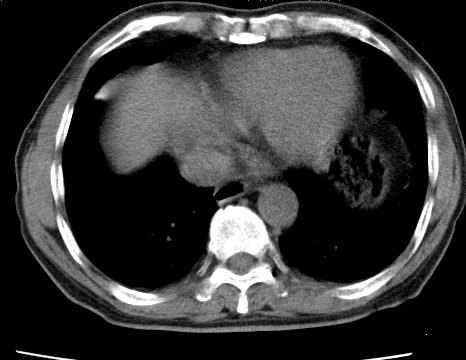

考虑右肺中叶不张,请大家发表意见

1右肺门旁类圆形肿块影,右肺中叶不张,建议纤支镜检查

2右侧胸膜增厚,右侧叶间胸膜区钙化

3右肺下叶小囊状透亮影考虑肺气肿

右肺中叶不张、肺门轮廓增大,占位不除外;建议增强,必要时支气管镜详查。

右肺中叶支气管闭塞,中叶肺不张,右侧肺门见肿块影。中心型肺癌的可能大。建议支气管镜检查。